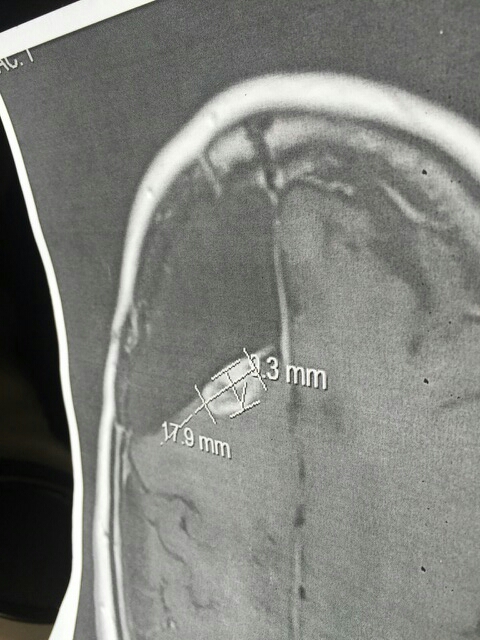

Medical Imaging Shared for Context

Medical imaging alone does not establish causation, treatment effect, or clinical outcome.